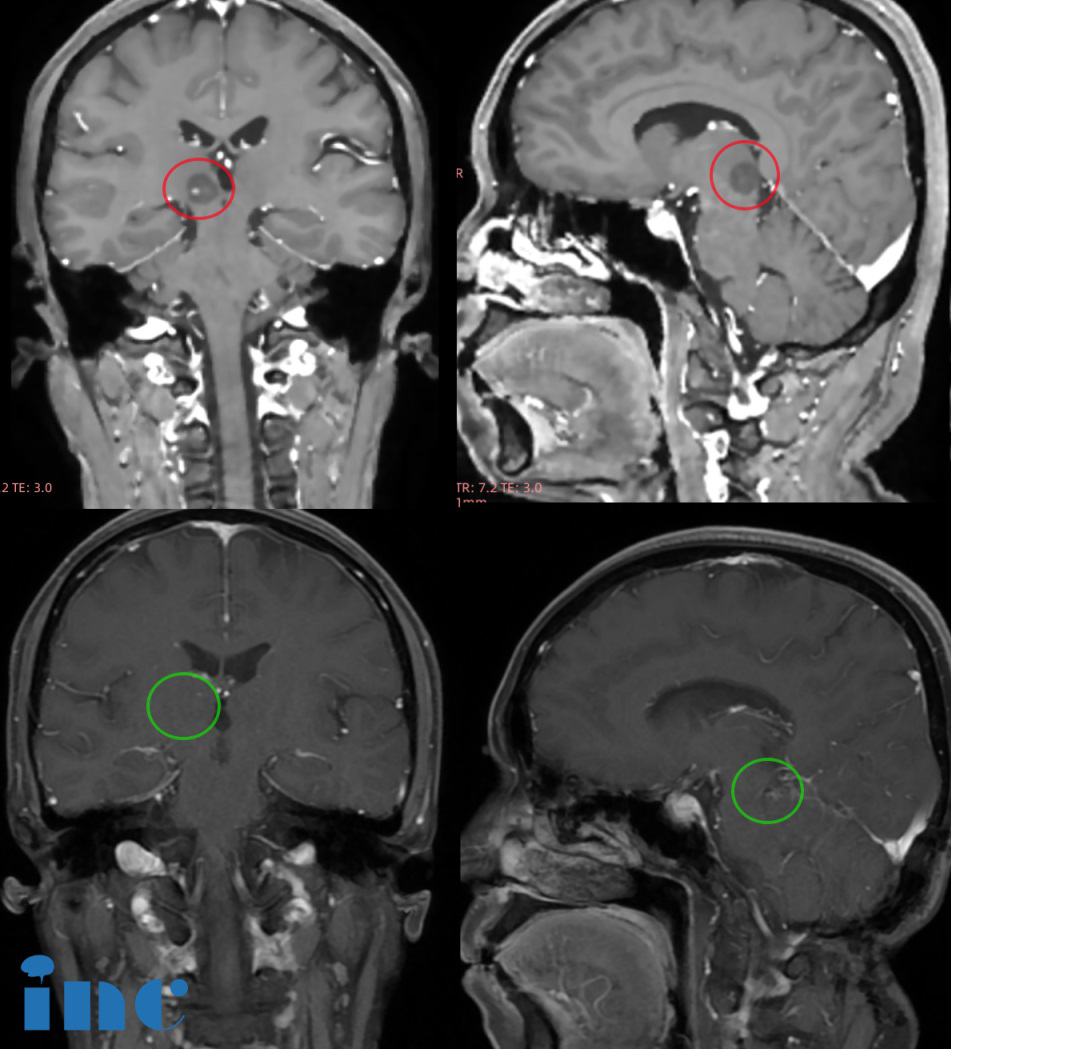

1999年7月因頭痛查出顱咽管瘤,并在2000年1月及4月的復(fù)查中發(fā)現(xiàn)腫瘤不斷生長。